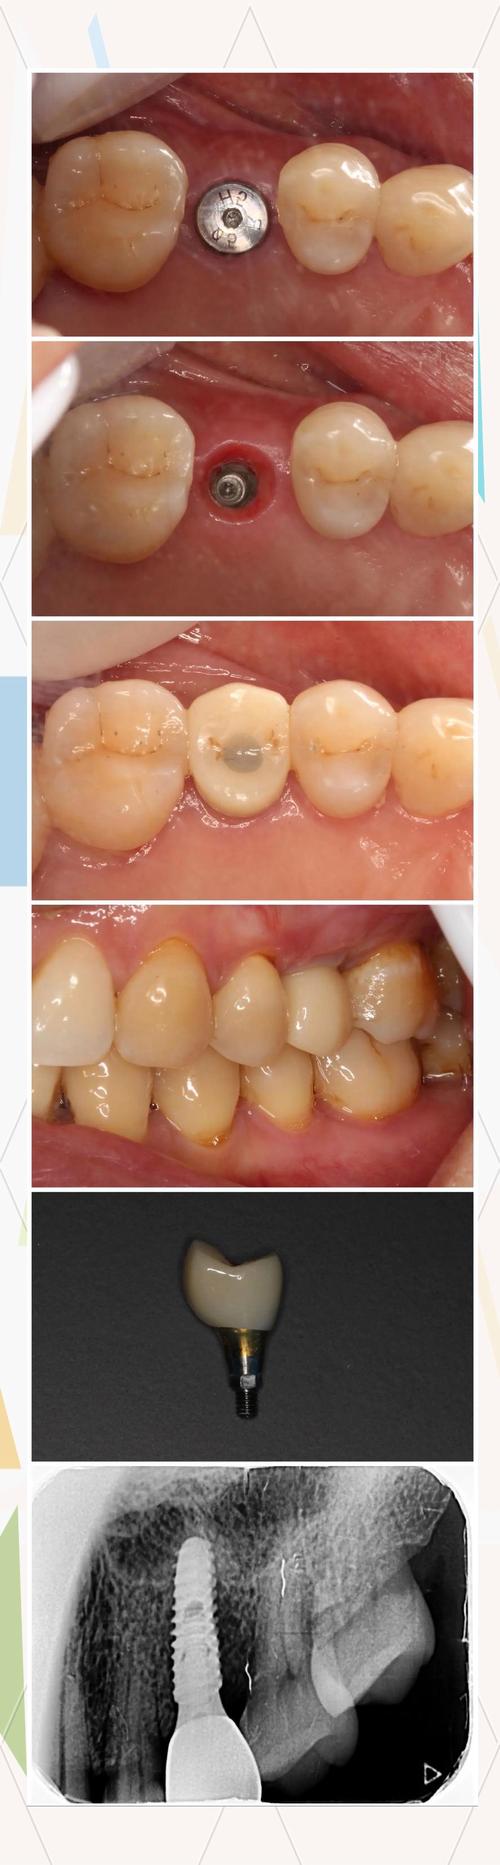

术后10天左右通常需要首次复诊(具体时间以医生交代为准),复诊目的包括:检查牙龈愈合情况、拆除缝线(若为可吸收缝线则无需拆除)、评估种植体稳定性、调整临时修复体(如有)、指导后续护理流程。

复诊准备:提前整理术后症状(如肿胀、疼痛变化规律,有无出血或异常感觉),携带手术病历和用药记录,复诊前1小时避免进食(若需拍摄X光片,需去除金属饰品),复诊时需如实告知医生感受,若有疑问(如饮食禁忌、清洁方式)可及时咨询,确保获得个性化指导。